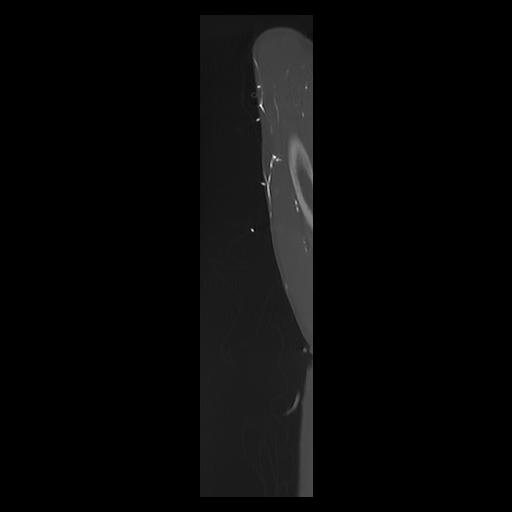

33 PULMON,CE,Sagittal,3.000,PULMON,Sagittal,